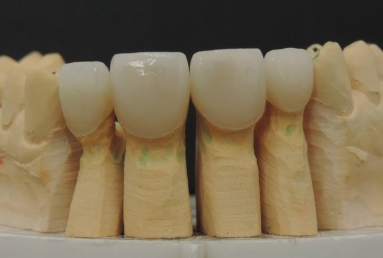

Very small lateral incisors covered with full ceramic crowns and ceramic veneers on central incisors. The prosthetic space was correctly split between the four incisors, in order to reduce the disproportion between the large centrals and the very small laterals. The preparation of the teeth was minimally invasive, all four incisors remained vital.